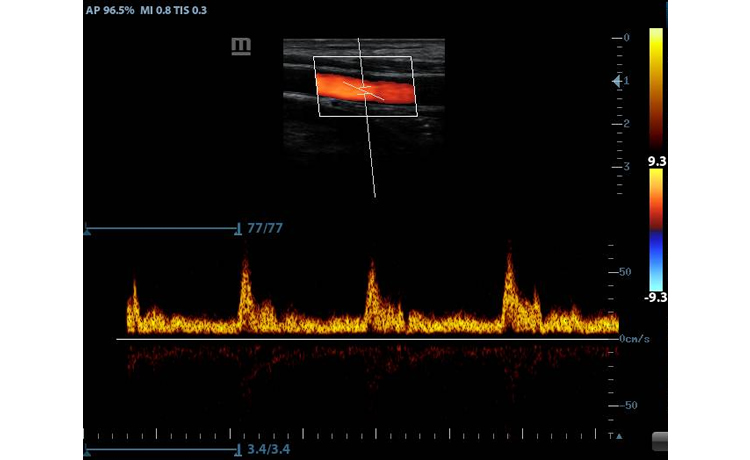

- PW Doppler and Auto Trace: Reveal details of blood flow for more comprehensive diagnosis

Clinical Images